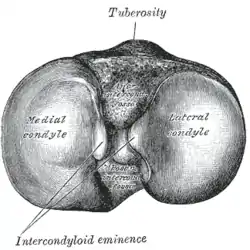

Articular bodies

The main articular bodies of the femur are its lateral and medial condyles. These diverge slightly distally and posteriorly, with the lateral condyle being wider in front than at the back while the medial condyle is of more constant width. [10]: 206 The radius of the condyles' curvature in the sagittal plane becomes smaller toward the back. This diminishing radius produces a series of involute midpoints (i.e. located on a spiral). The resulting series of transverse axes permit the sliding and rolling motion in the flexing knee while ensuring the collateral ligaments are sufficiently lax to permit the rotation associated with the curvature of the medial condyle about a vertical axis.[10]: 194–95

The pair of tibial condyles are separated by the intercondylar eminence[10]: 206 composed of a lateral and a medial tubercle.[10]: 202